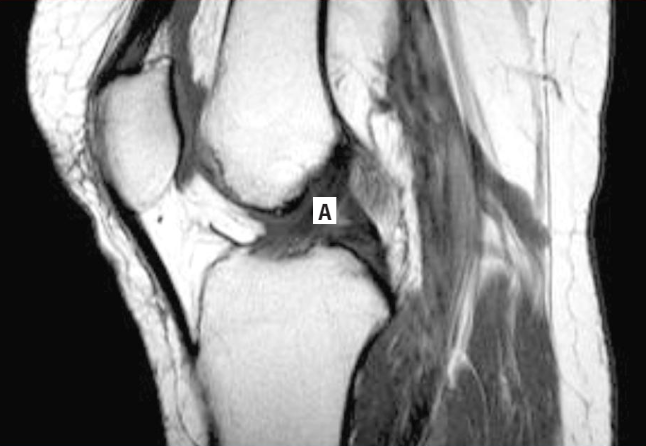

Paciente hombre de 24 años de edad que acude a consulta de traumatología por presentar dolor en la articulación de la rodilla, derrame articular e imposibilidad para realizar movimientos amplios de flexión. El paciente refiere que durante un partido de futbol recibió una barrida que golpeó la rodilla de apoyo por la cara externa y que fue entonces cuando apareció el dolor. Se realiza una exploración física de la siguiente manera: para valorar los meniscos se pide al paciente que se coloque en decúbito supino, se flexiona la rodilla y se coloca el dedo en el borde del menisco, seguido de una extensión en rotación interna y luego se repite en rotación externa; como consecuencia, se despierta dolor y se siente un chasquido en el menisco interno al extender la rodilla en rotación lateral. Para valorar los ligamentos colaterales se extiende la rodilla y se aplica un movimiento de empuje hacia la cara medial con la finalidad de valorar la integridad del menisco lateral, y se empuja desde afuera para valorar el menisco interno; ante ello, se observa una leve abertura en la cara interna de la rodilla, el signo del bostezo. Para valorar los ligamentos cruzados se realizan las pruebas de rutina, las cuales fueron negativas. Se toma una radiografía anteroposterior de la rodilla y una resonancia magnética (RM), donde se confirma una lesión en el menisco interno. Se decide puncionar la articulación para drenar el derrame articular.